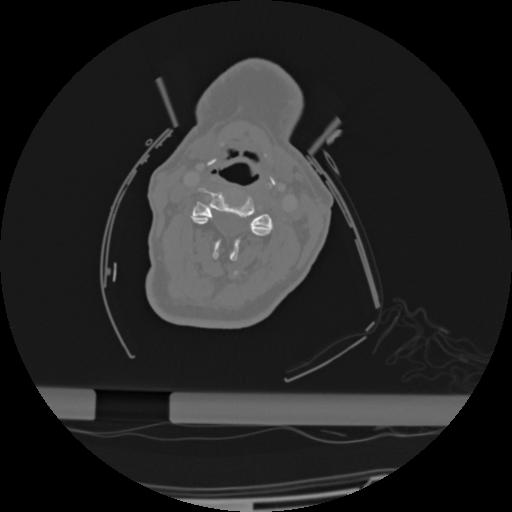

22 ANGIO,CE,Vol,0.5,ANGIO,,